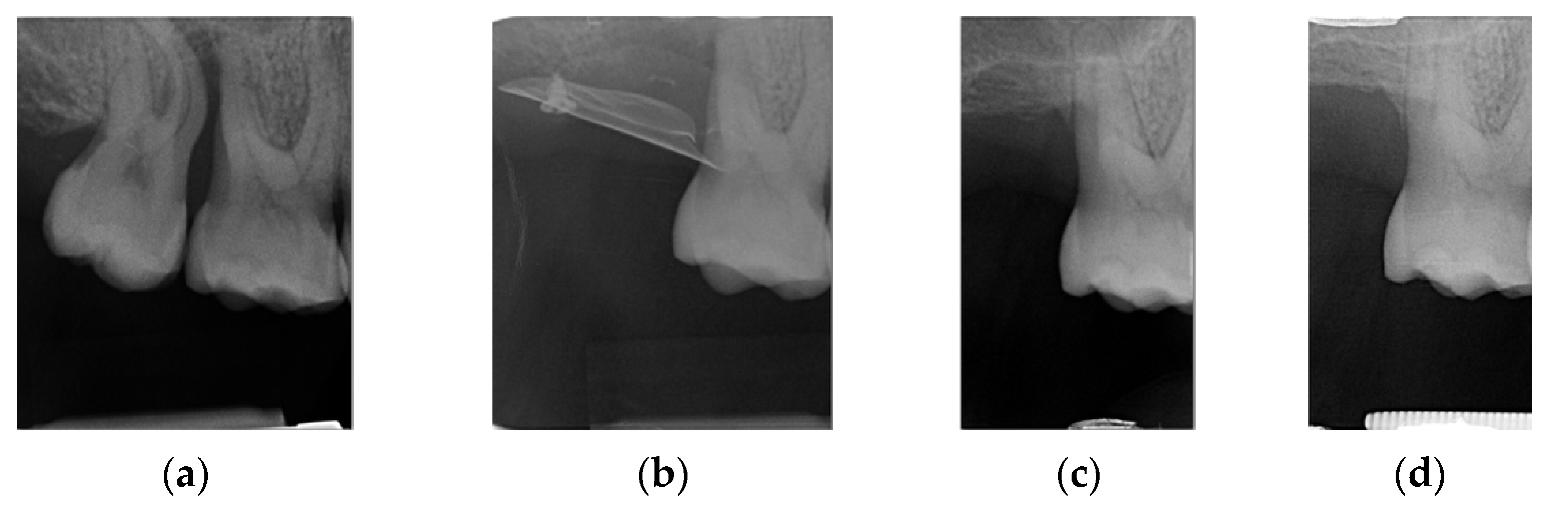

4.1. Clinical Case n.1.